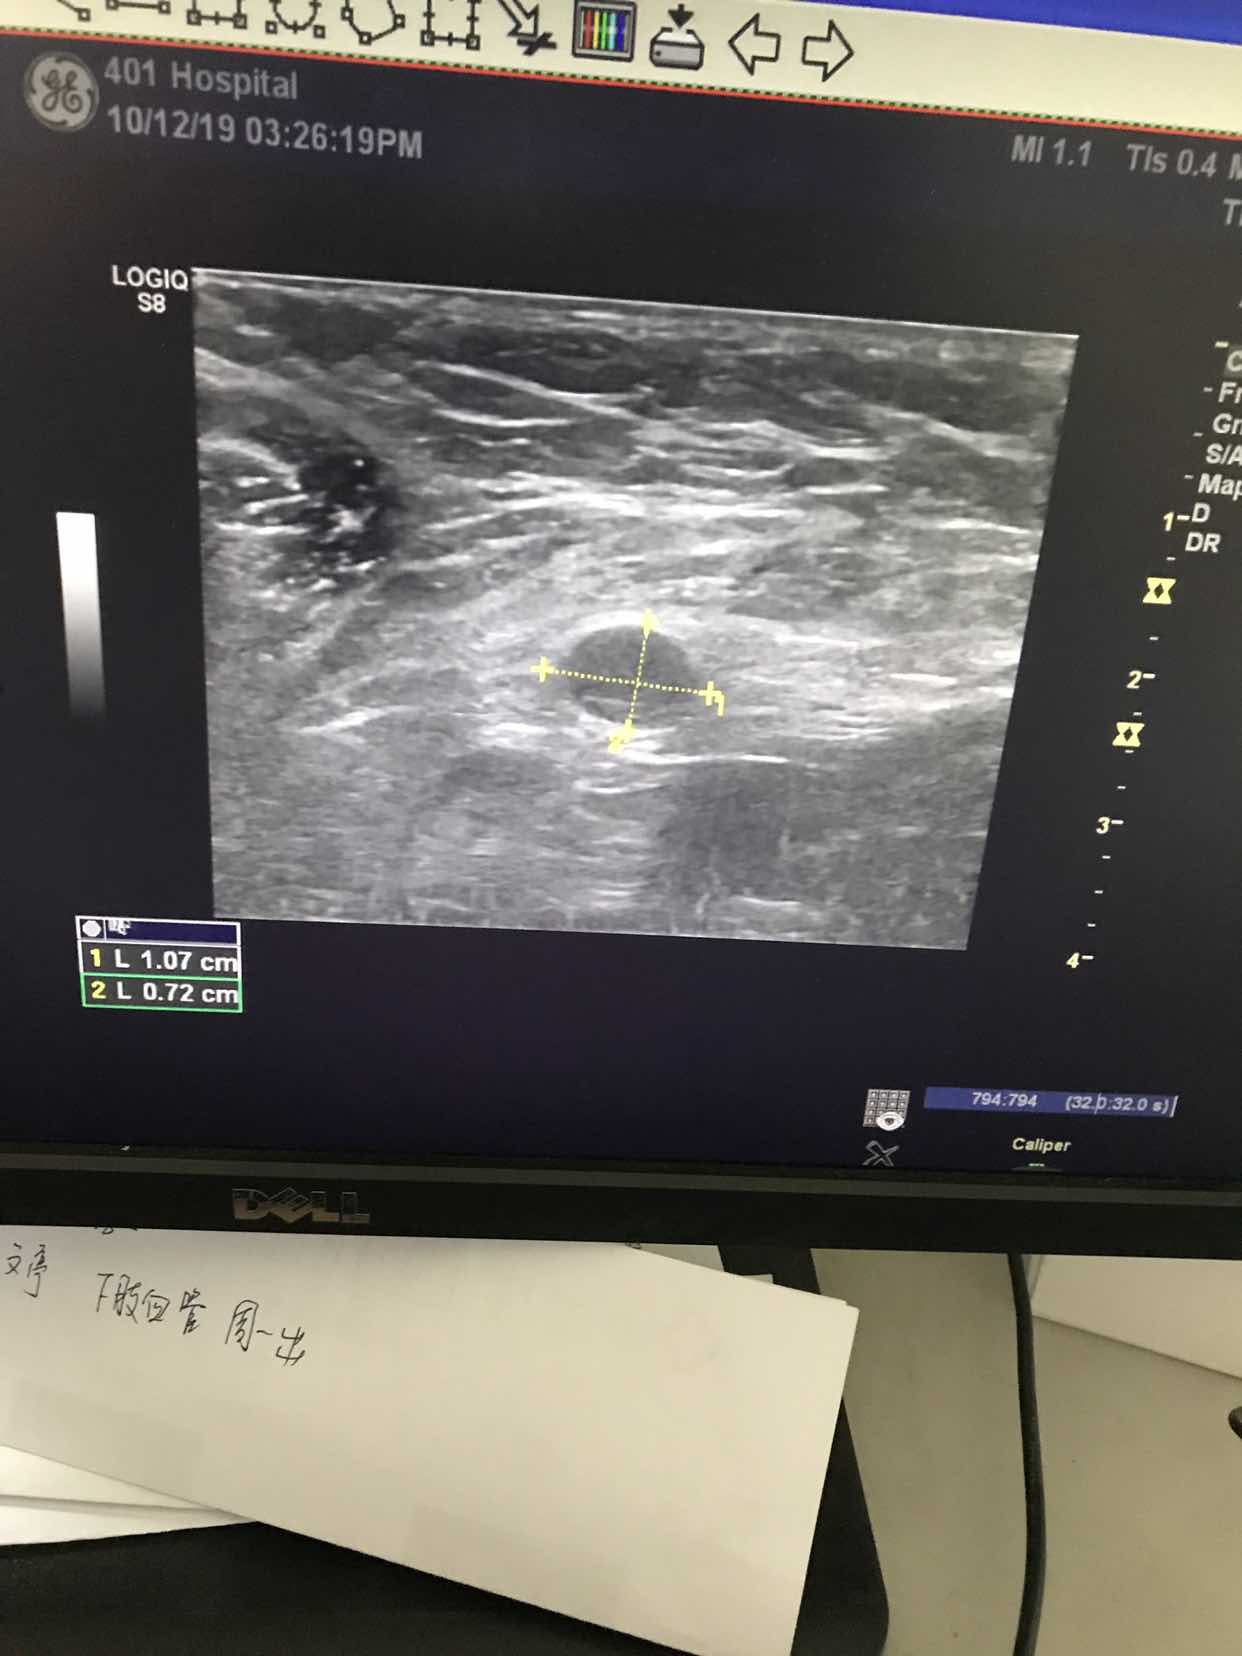

是淋巴吗?多大啊?报告怎么说的